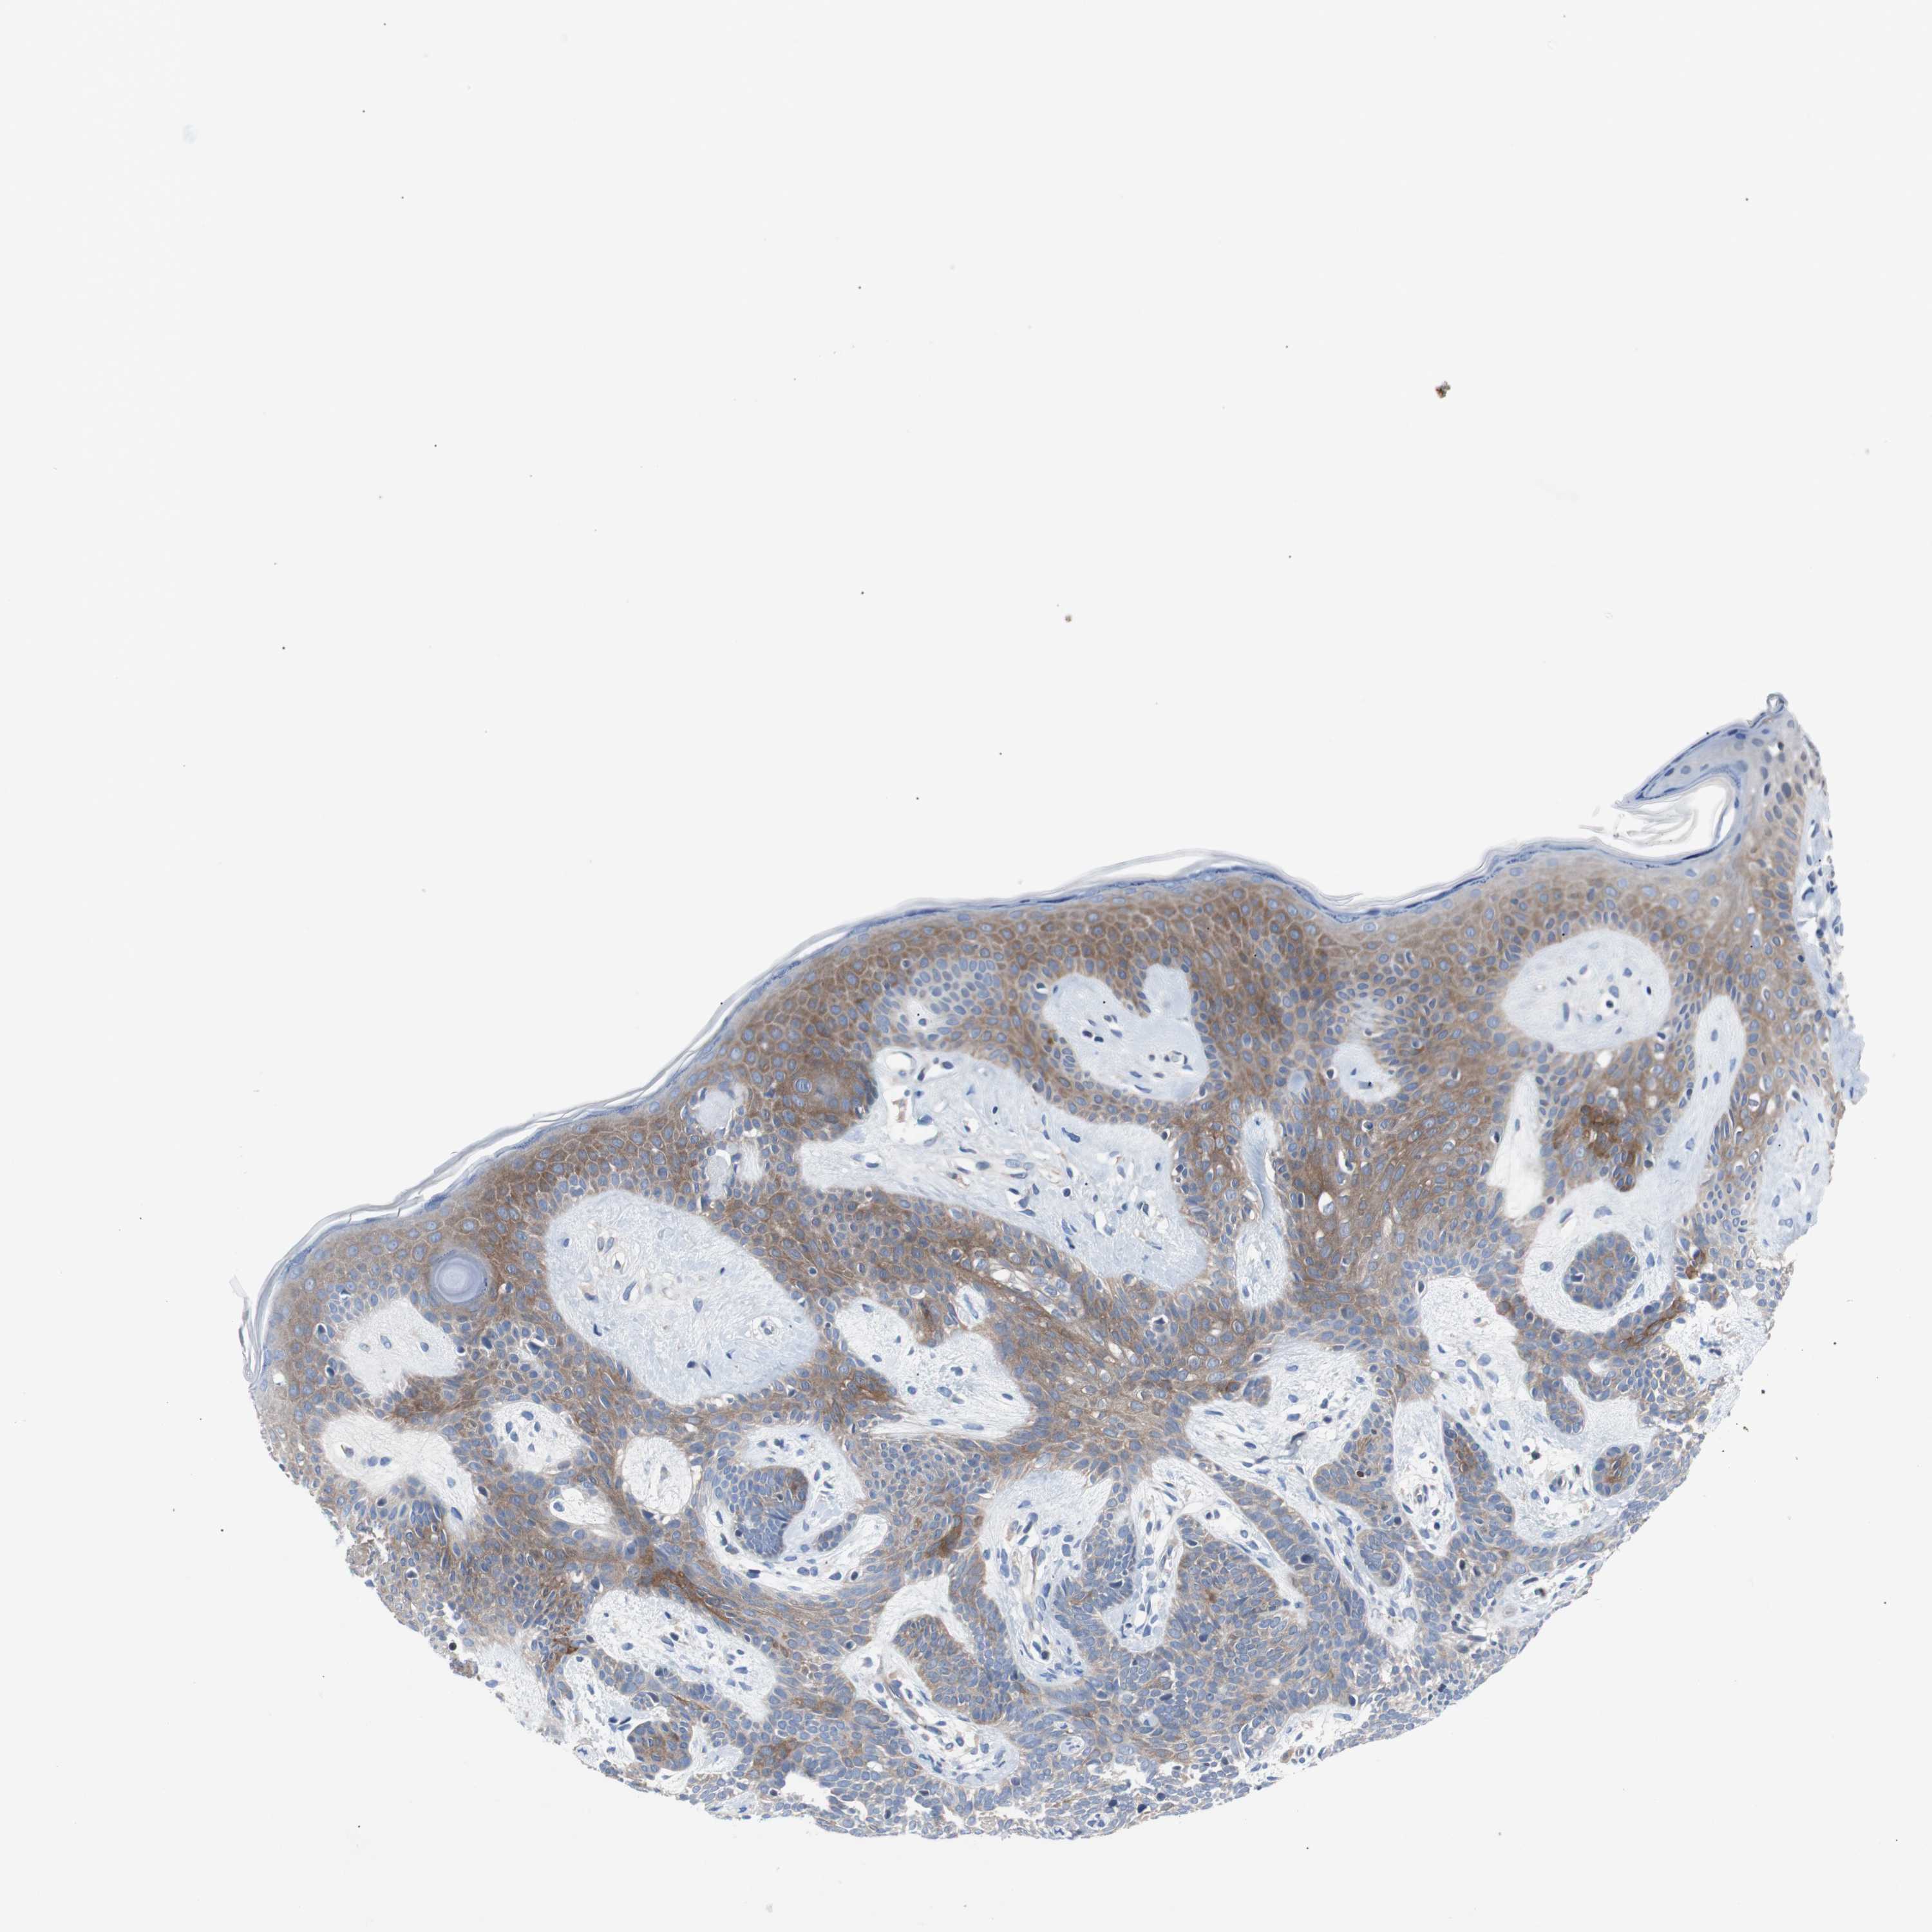

CANCER SKIN CANCER Show tissue menu

Basal cell and squamous cell cancer

SKIN CANCER - Protein expressioni

A mouse-over function shows sample information and annotation data. Click on an image to view it in a full screen mode. Samples can be filtered based on level of antibody staining by selecting one or several of the following categories: high, medium, low and not detected. The assay and annotation is described here.

Each image is clickable and will lead to virtual microscopy that enables deeper exploration of all samples and also displays staining intensity scores, fraction scores and subcellular localization as well as patient and tissue information for each sample.

Antibody CAB007818

Staining

High

Strong

Moderate

>75%

75%-25%

Location

Cytoplasmic/membranous

Basal cell carcinoma

Papilloma, NOS